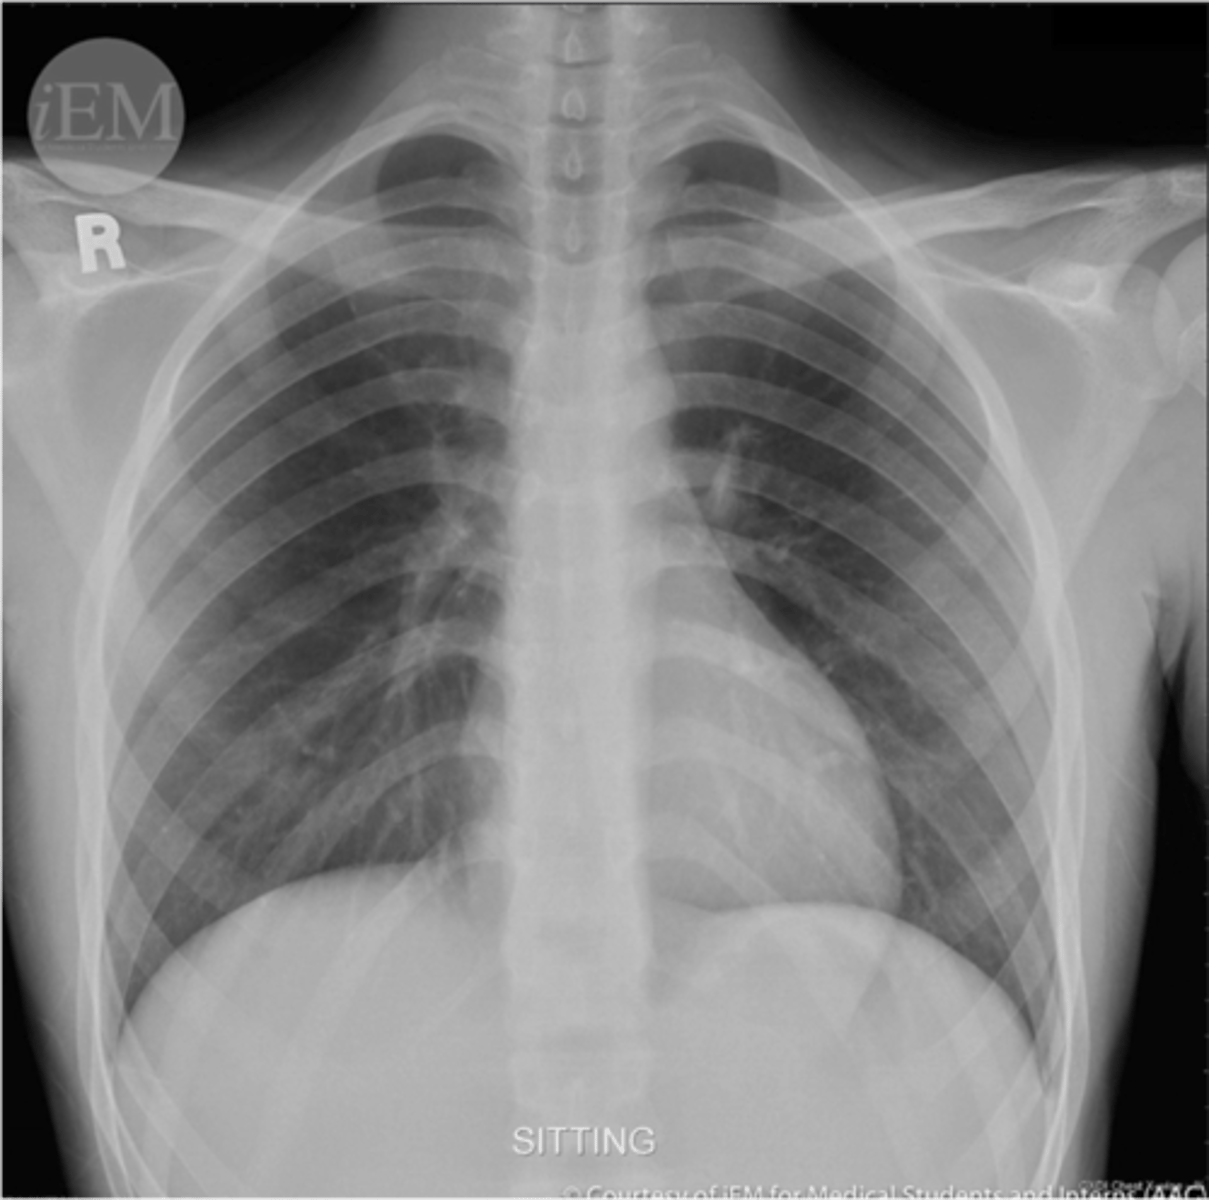

-pleural effusion (fluid will go to the bottom)

-pneumothorax (air will rise to top)

Lateral decubitus view is helpful in diagnosing what

-blunts costophrenic angles

-haze over entire hemithorax (densest at base)

Pleural effusion on an XR